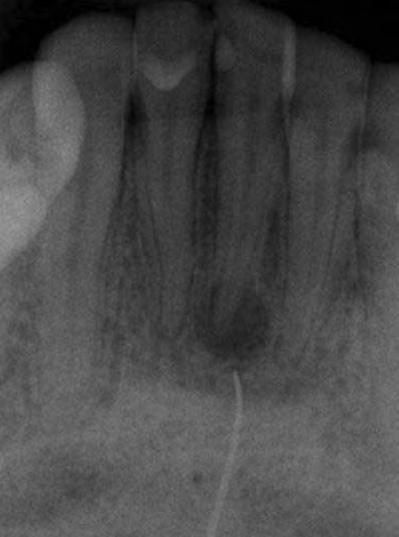

The pathway of a sinus tract that develops from a necrotic pulp is through the alveolar bone and emptying purulent exudate into the oral cavity. The stoma can be on the attached gingiva, alveolar mucosa or gingival sulcus. It can also empty on the buccal or lingual surface (Figures 1A, B). This is determined by the proximity of the apex to either the cortical plate and/or the density of the bone. Finally, it can also drain extraorally (cutaneous sinus tract) (Figures 2A, B).[3-5]

Figure 1B: Sinus tract was traced with size 35 gutta-percha. Periapical radiograph revealed origin of sinus tract was periapical lesion associated with distal root of first molar not second molar, indicating possibly wrong tooth had been treated. Figure 1A: Patient was referred to endodontist for evaluation because sinus opening had not healed after endodontic therapy on lower left second molar. Patient was asymptomatic and had been so prior to initiation of therapy; however treatment was initiated because of diagnosis of sinus tract opening facial to second molar

Figure 2B: By gently removing existing scab, sinus opening was evident. It was traced with size #25 gutta-percha cone to lower right central incisor that was unresponsive to cold and EPT. Figure 2A: Patient reported to clinic with history of persistent “pimple” on her chin. Plastic surgeon had excised pimple, but it reappeared within few weeks. fistula is lined with epithelium that may or may not be filled by granulomatous tissue.[22-26]